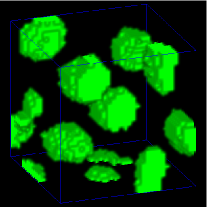

Our proposed method was compared to other 3D segmentation methods including 3D active surface [7], 3D active surface with inhomogeneity correction [8], 3D Squassh [9, 10], 3D encoder-decoder architecture [20], 3D encoder-decoder architecture with CycleGAN. Three original 3D subvolumes of Data-I were selected to evaluate the performance of our proposed method. We denote the original volume as subvolume (), subvolume (), and subvolume (), respectively. Corresponding groundtruth of each subvolume was hand segmented. Voxx [29] was used to visualize the segmentation results in 3D and compared to the manually annotated volumes. In Figure 5, 3D visualizations of the hand segmented subvolume and the corresponding segmentation results for various methods were presented. As seen from the 3D visualization in Figure 5, our proposed method shows the best performance among presented methods visually compared to hand segmented groundtruth volume. In general, our proposed method captures only nuclei structure whereas other presented methods falsely detect non-nuclei structures as nuclei. Note that segmentation results in Figure 5 yields smaller segmentation mask and suffered from location shift. Our proposed method shown in Figure 5 outperforms Figure 5 since our proposed method uses spatially constrained CycleGAN and takes consideration of the Dice loss and the binary cross-entropy loss.

To make this clear, segmentation results were color coded using 3D connected component labeling and overlaid on the original volumes. The method from [20] cannot distinguish between nuclei and non-nuclei structures including noise. This is especially recognizable from segmentation results of Data-I in which multiple nuclei and non-nuclei structures are colored with the same color. As can be observed from Figure 6 and 6, segmentation masks are smaller than nuclei size and suffered from location shifts. Conversely, our proposed method shown in Figure 6 and 6 segments nuclei with the right shape at the correct locations.